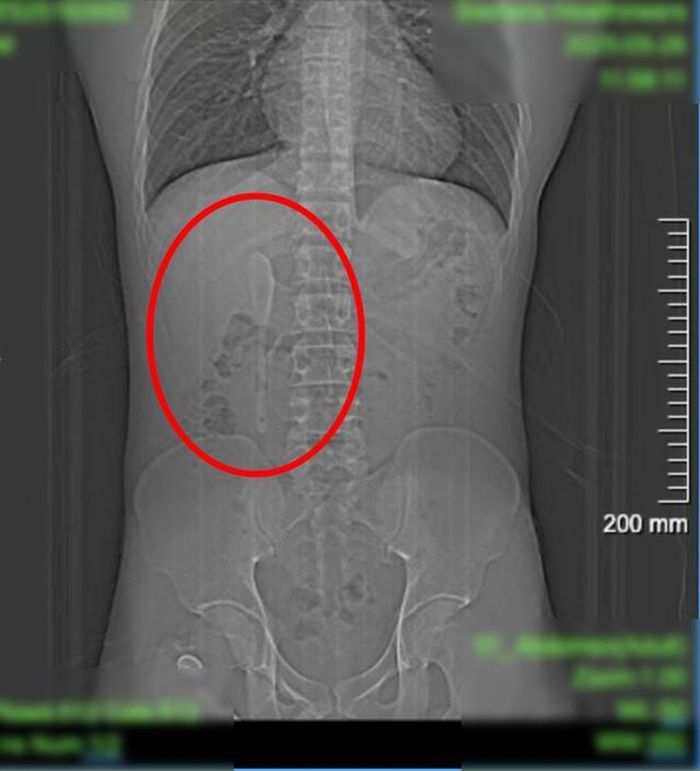

Các bác sĩ đã tiến hành khám sức khỏe và chụp CT để tìm nguyên nhân. Lúc đầu, bệnh nhân nghĩ rằng mình đã vô tình nuốt phải một vật bằng nhựa. Tuy nhiên, những gì họ tìm thấy là một chiếc thìa gốm dài 15 cm mắc kẹt trong tá tràng.

Kết quả chụp CT của người đàn ông cho thấy có một vật thể hình thìa dài gần 15 cm nằm bên trong cơ thể anh ta. Ảnh: Bệnh viện Trung Sơn

Bác sĩ Chu Bình Hồng, giám đốc trung tâm nội soi Bệnh viện Trung Sơn cho biết, thìa có bề mặt nhẵn và mỏng. Chiếc thìa bị kẹt ở chỗ nối giữa phần mở rộng của ruột non và thực quản, đây là một khu vực rất hẹp. Nếu không nhanh chóng lấy ra, có thể gây thủng ruột hoặc chảy máu trong nghiêm trọng.